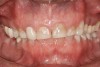

Figure 2   Asymmetric tooth wear in a bruxism triad patient as a result of friction from bruxing, poor salivary lubrication as a byproduct of medication, and roughened surfaces created as a result of erosive reflux.

Figure 2